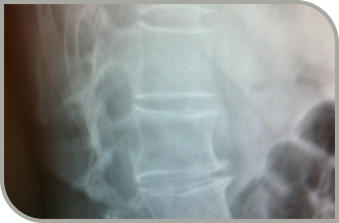

Kurse